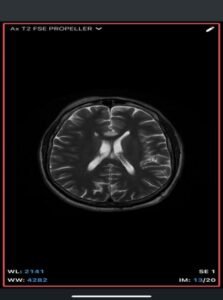

Intracranial dermoid cyst

A rare, congenital, benign lesion composed of mature adipose tissue located within the pericallosal cistern, closely related to the corpus callosum. It is a developmental anomaly rather than a true neoplasm.

Imaging Findings-

- MRI

- T1-weighted: Hyperintense (fat signal).

- T2-weighted: Variable, usually hyperintense; may show chemical shift artifacts.

- Fat-suppressed sequences: Complete signal suppression confirms fat composition.

- Post-contrast: No enhancement.

- Often associated with:

- Corpus callosum agenesis/dysgenesis

- Interhemispheric cysts